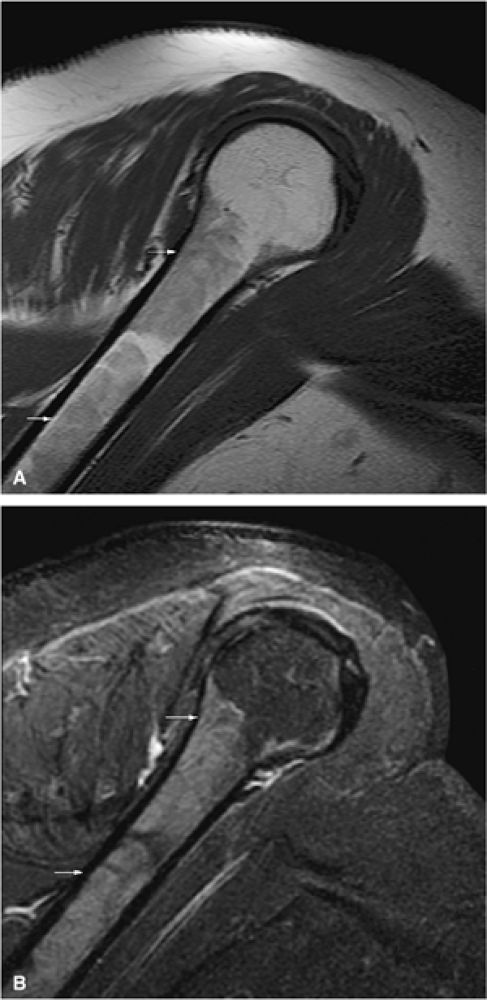

|

FIGURE 13.64 ● Metastatic breast cancer involving the shoulder. (A) Diffuse hypointense marrow replacement is seen on a sagittal T1-weighted image (arrows). (B) Metastatic tumor is better visualized on the coronal STIR image (white arrows). Uninvolved marrow is hypointense (black arrows).